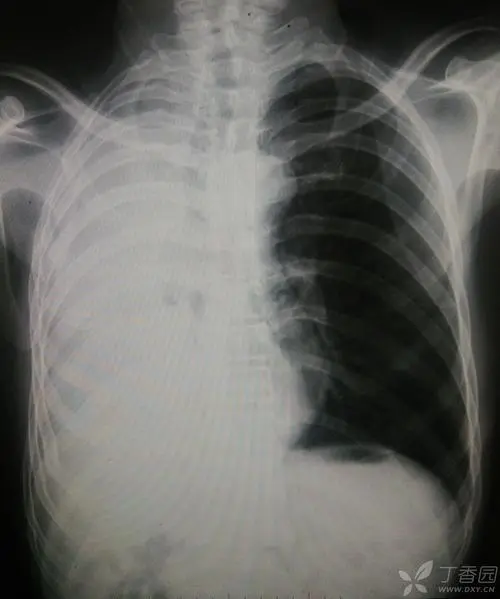

首先要明确一点,"白肺"只是医学临床工作上的一种口语化的表达方式。通常患者肺部出现炎症,并且随着炎症逐渐加重,肺部也会出现越来越多发白的情况。通常情况下,在CT影像中,如果白色区域超过75%,通常就会称其为"白肺"。

"白肺"指代的是比较严重的肺部感染问题,但并不是只有新冠病毒会导致"白肺"。普通的肺炎,肺部感染问题,只要感染较为严重同样有可能导致"白肺","白肺"并不是新冠病毒感染的标志,这一点我们需要注意区分。